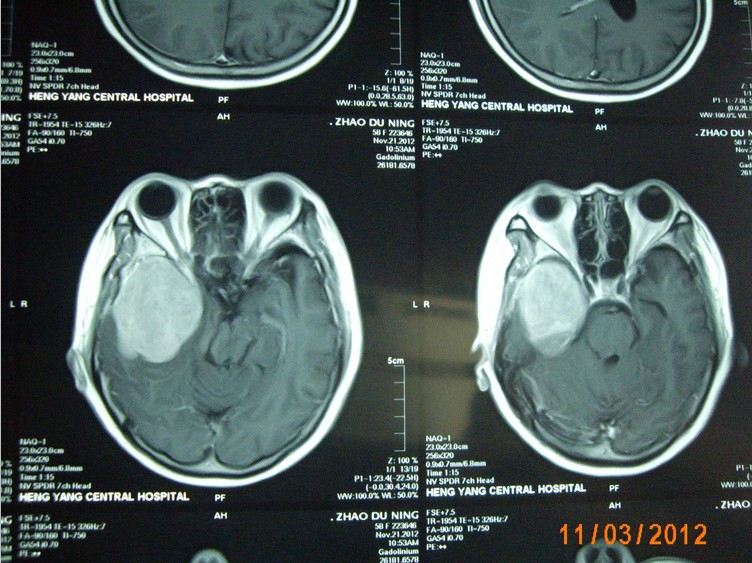

近日,一名來自常寧的58歲女性患者,因右側(cè)肢體麻木,頭暈3月入住衡陽(yáng)市中心醫(yī)院神經(jīng)外科。頭顱增強(qiáng)磁共振檢查明確右側(cè)中顱窩底巨大腦膜瘤,約10*6*5cm3大小。經(jīng)過嚴(yán)密的術(shù)前檢查和全科術(shù)前討論,以科室主任鐘三寶主任醫(yī)師為首的手術(shù)組經(jīng)過4個(gè)小時(shí)的顯微鏡下手術(shù),順利的全切腫瘤。因腫瘤巨大,瘤體切除后局部留下一很大空腔,容易并發(fā)腦組織移位、腦出血,導(dǎo)致嚴(yán)重并發(fā)癥。術(shù)者創(chuàng)新地使用了水囊,逐步減壓等方法,使患者平穩(wěn)地度過了腦組織復(fù)位關(guān)。術(shù)后未出現(xiàn)任何并發(fā)癥,恢復(fù)良好,順利出院。

(術(shù)前磁共振)